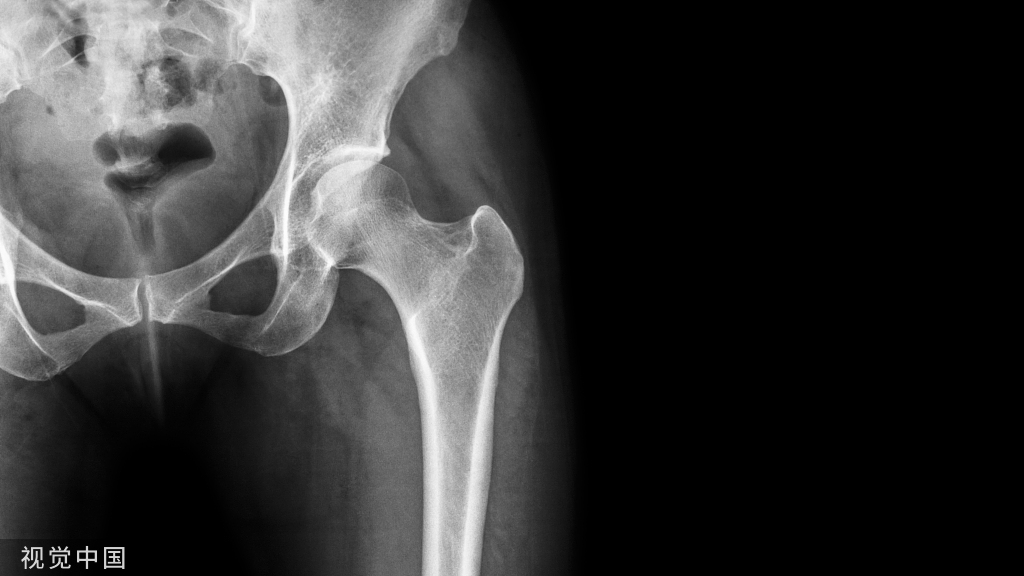

影像学检查X线片:股骨头位于髋臼的外上方、有无合并髋臼后缘骨折X线表现:后脱位股骨头变小,股骨头变大。后脱位时,小转子有可能因为肢体的内旋而不可见。前脱位时,小转子可因肢体的外旋而全部显现。

髋关节前脱位诊断:患肢呈明显外展、外旋、屈曲及延长畸形在闭孔或腹股沟附近可触到股骨头X线片:股骨头在闭孔内或耻骨上支附近